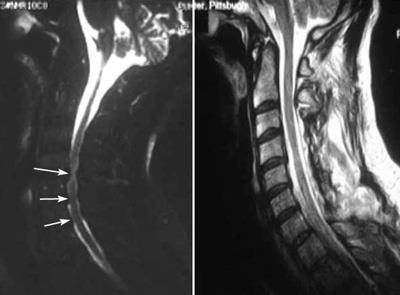

MRI scans of spinal cord compression and laminoplasty

(Left) This MRI scan shows both anterior and posterior spinal cord compression (arrows). (Right) An MRI scan of the same patient after laminoplasty shows increased space in the spinal canal.

Reproduced from Cornett CA, Braly BA, Kang J, Donaldson, WF: Laminectomy and fusion and laminoplasty: indications and techniques. Orthopaedic Knowledge Online Journal 2012; 10(1). Accessed July 2015.